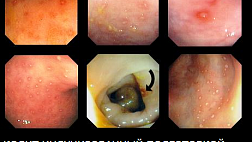

Большие стигматы остановившегося кровотеченияНет Черные пятна

Кровь в полости.

Тромб.

Некровоточащие видимые сосуды. Фонтанирующее кровотечение